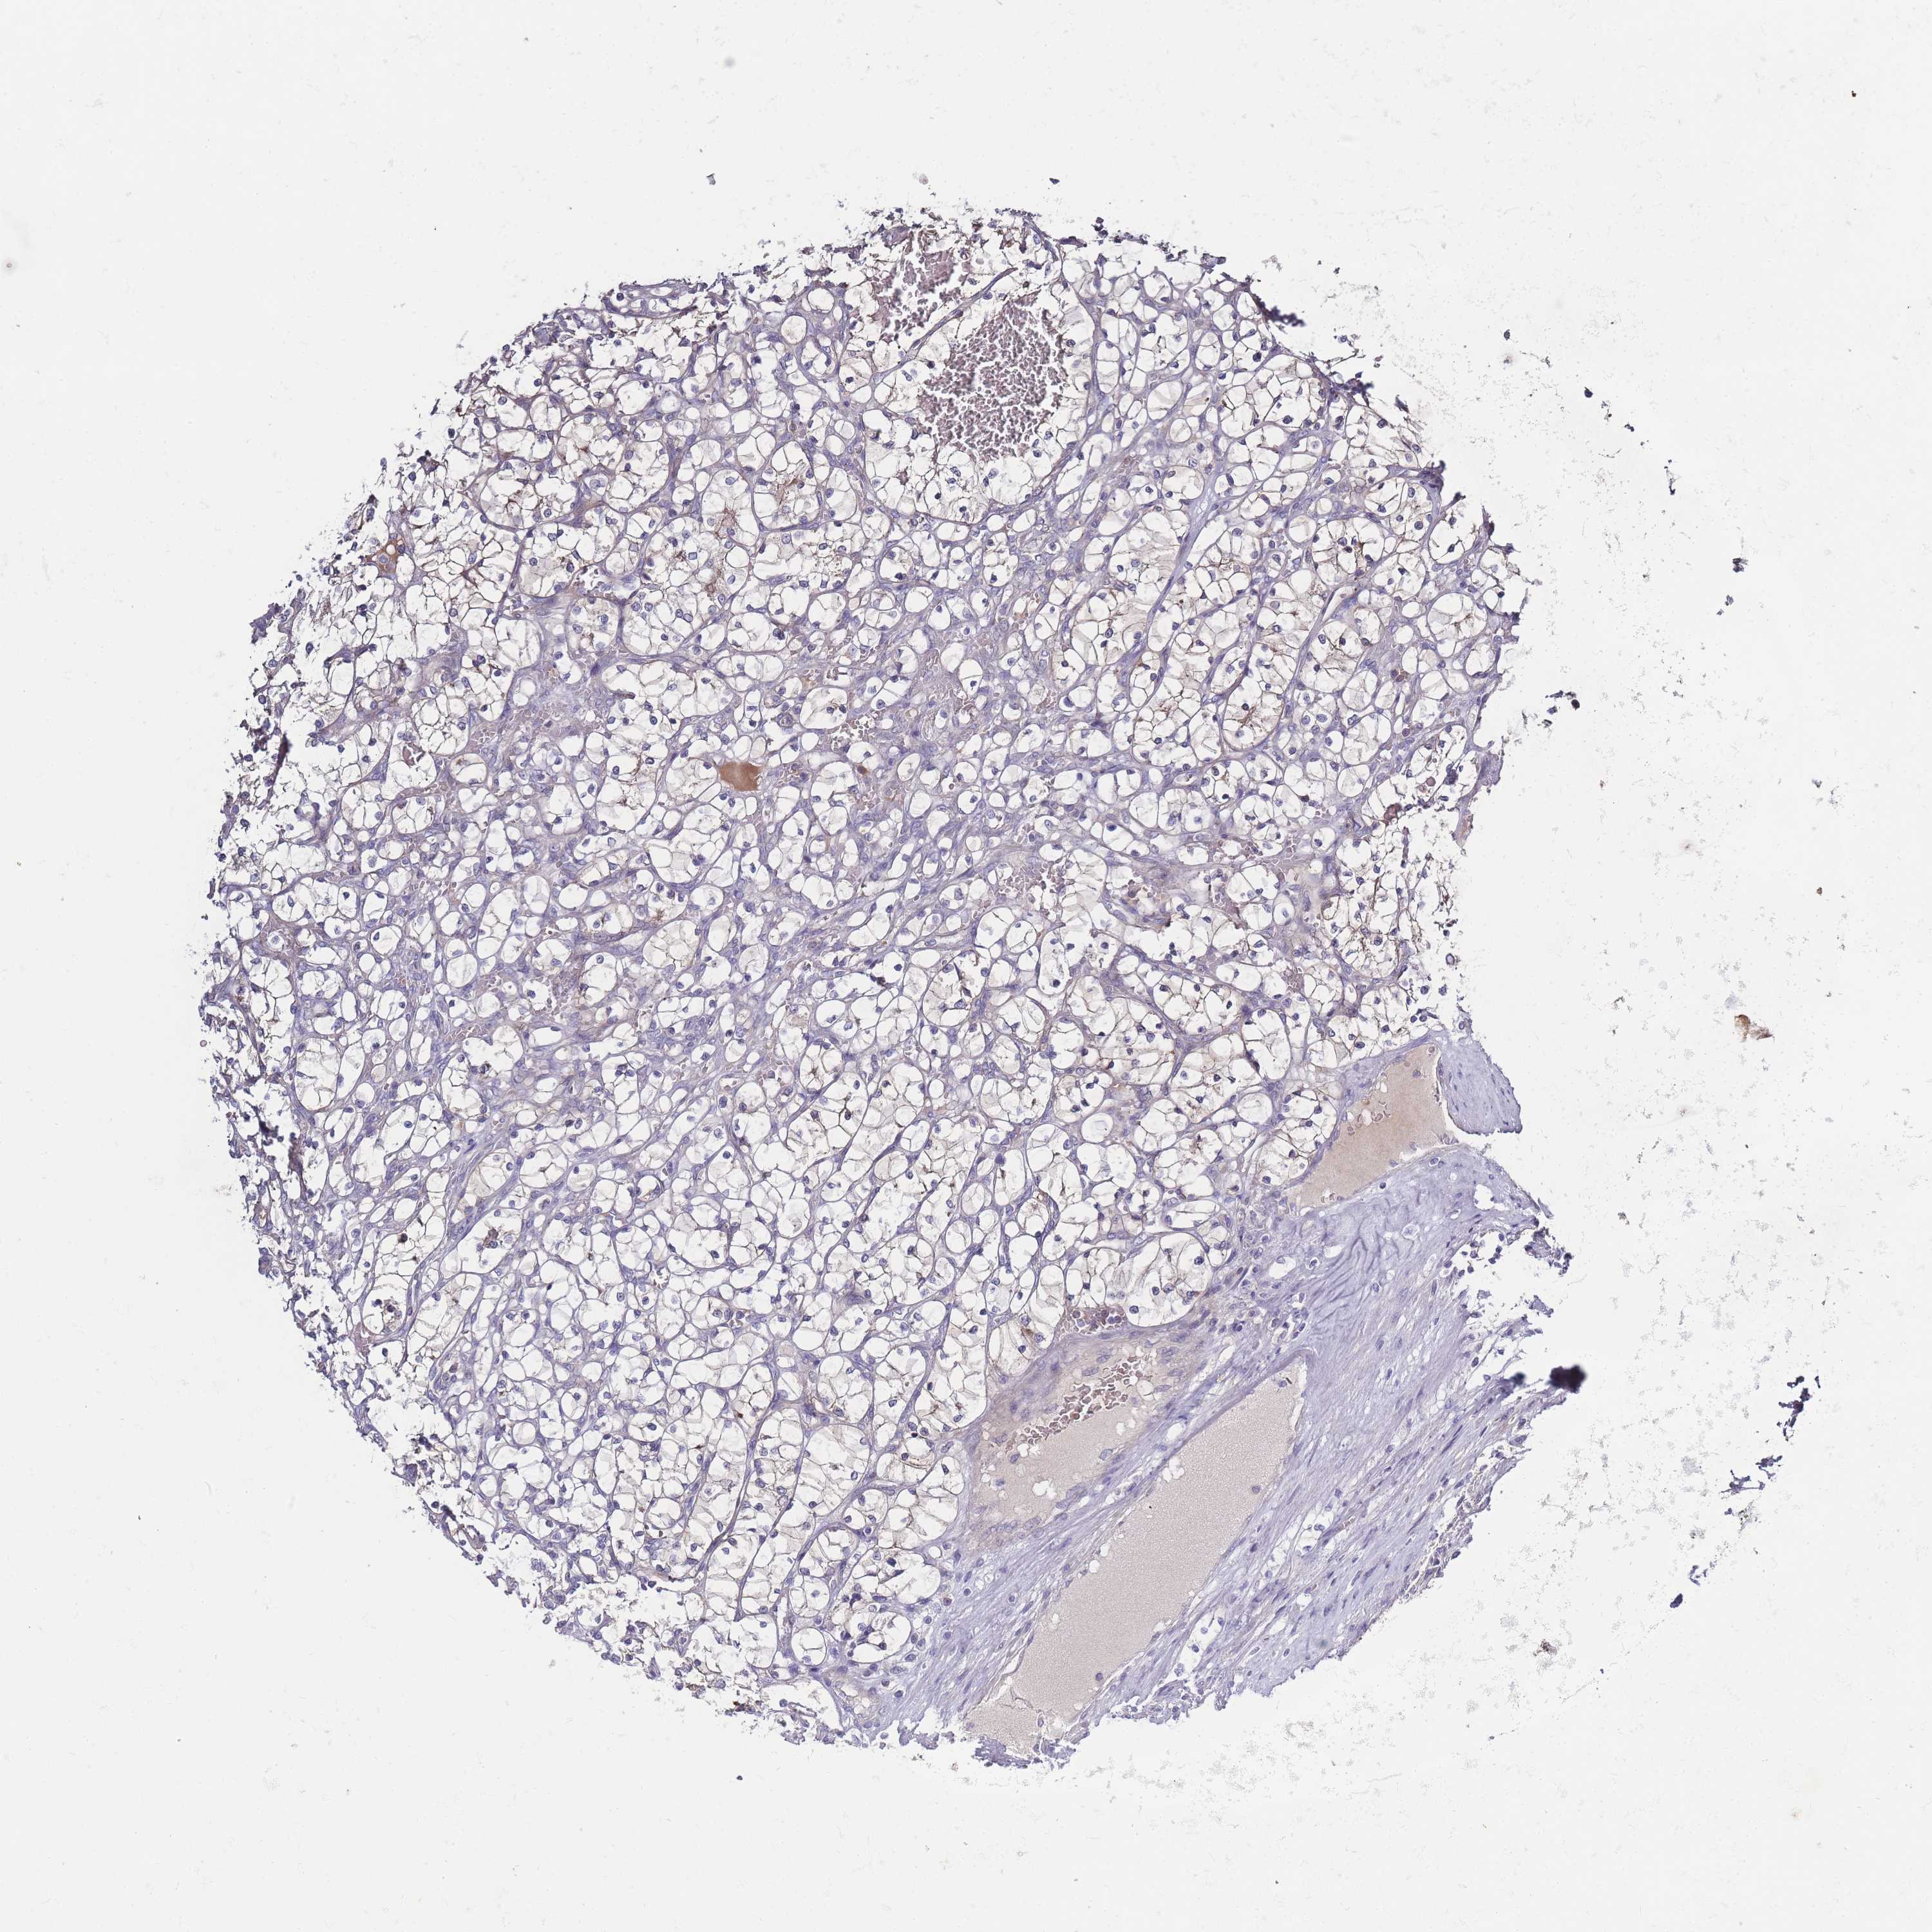

KIDNEY RENAL CLEAR CELL CARCINOMA (VALIDATION) - Interactive survival scatter ploti

The Survival Scatter plot shows the clinical status (i.e. dead or alive) for all individuals in the patient cohort, based on the same data that underlies the corresponding Kaplan-Meier plots. Patients that are alive at last time for follow-up are shown in blue and patients who have died during the study are shown in red.

The x-axis shows the expression levels (FPKM) of the investigated gene in the tumor tissue at the time of diagnosis. The y-axis shows the follow-up time after diagnosis (years). Both axes are complimented with kernel density curves demonstrating the data density over the axes. The top density plot shows the expression levels (FPKM) distribution among dead (red) and alive patients (blue). The right density plot shows the data density of the survived years of dead patients with high and low expression levels respectively, stratified using the cutoff indicated by the vertical dashed line through the Survival Scatter plot. This cutoff is automatically defined based on the FPKM cutoff that minimizes the p-score. The cutoff can be changed by dragging the vertical line or by entering a cutoff value in the square labeled "Current cut-off".

Under the Survival Scatter plot the p-score landscape (black curve; left axis) is shown together with dead median separation (red curve; right axis). Dead median separation is the difference in median mRNA expression between patients who have died with high and low expression, respectively. It is calculated as follows: median FPKM expression of dead patients with high expression - median FPKM expression of dead patients with low expression. This is intended to aid the user in visually exploring custom cutoffs and the associated p-scores and dead median separation.

Individual patient data is displayed and can be filtered by clicking on one or more of the category buttons on the top of the page. Categories describing expression level and patient information include: high, low, alive, dead, female, male and tumor stages. The scale of the x-axis can be toggled between linear and log-scale by clicking on the "x log" button. Mouse-over function shows TCGA ID, patient information and mRNA expression (FPKM) for each patient.

& Survival analysisi

Kaplan-Meier plots summarize results from analysis of correlation between mRNA expression level and patient survival. Patients were divided based on level of expression into one of the two groups "low" (under cut off) or "high" (over cut off). X-axis shows time for survival (years) and y-axis shows the probability of survival, where 1.0 corresponds to 100 percent.

Survival analysis data not available.

TCGA RNA samplesi

RNA-seq data is reported as average FPKM (number Fragments Per Kilobase of exon per Million reads), generated by the The Cancer Genome Atlas (TCGA) .

Normal distribution across the dataset is visualized with box plots, shown as median and 25th and 75th percentiles. Points are displayed as outliers if they are above or below 1.5 times the interquartile range. FPKM values of the individual samples are presented next to the box plot.

Average pTPM 0.0

Number of samples 100